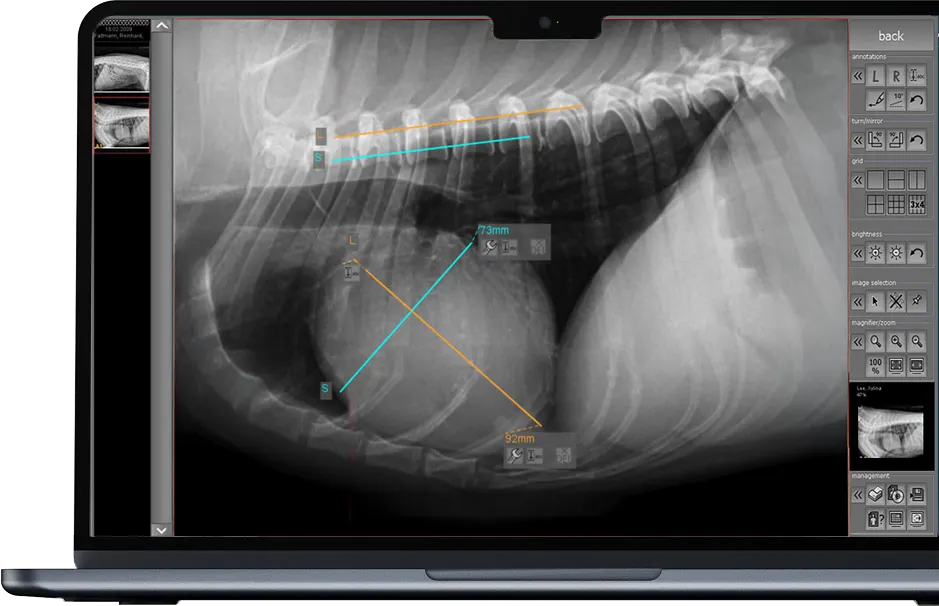

dicomPACS®DX-R es el corazón de nuestros sistemas OR 4Vet: con manejo inteligente, soporte de IA, radiografía dinámica y control inalámbrico, perfectamente adaptado a la medicina veterinaria moderna. Un software de adquisición y diagnóstico rápido y fiable que le apoya de manera óptima en la práctica diaria.

dicomPACS®MobileView es un sistema basado en la web que permite la visualización y edición de datos de imágenes radiológicas en dispositivos móviles, independientemente de la ubicación

La potente solución de software para la medicina veterinaria facilita la adquisición, el procesamiento, el archivado y la transmisión de material de imagen, con un manejo intuitivo y compatible con los sistemas habituales de gestión de clínicas.